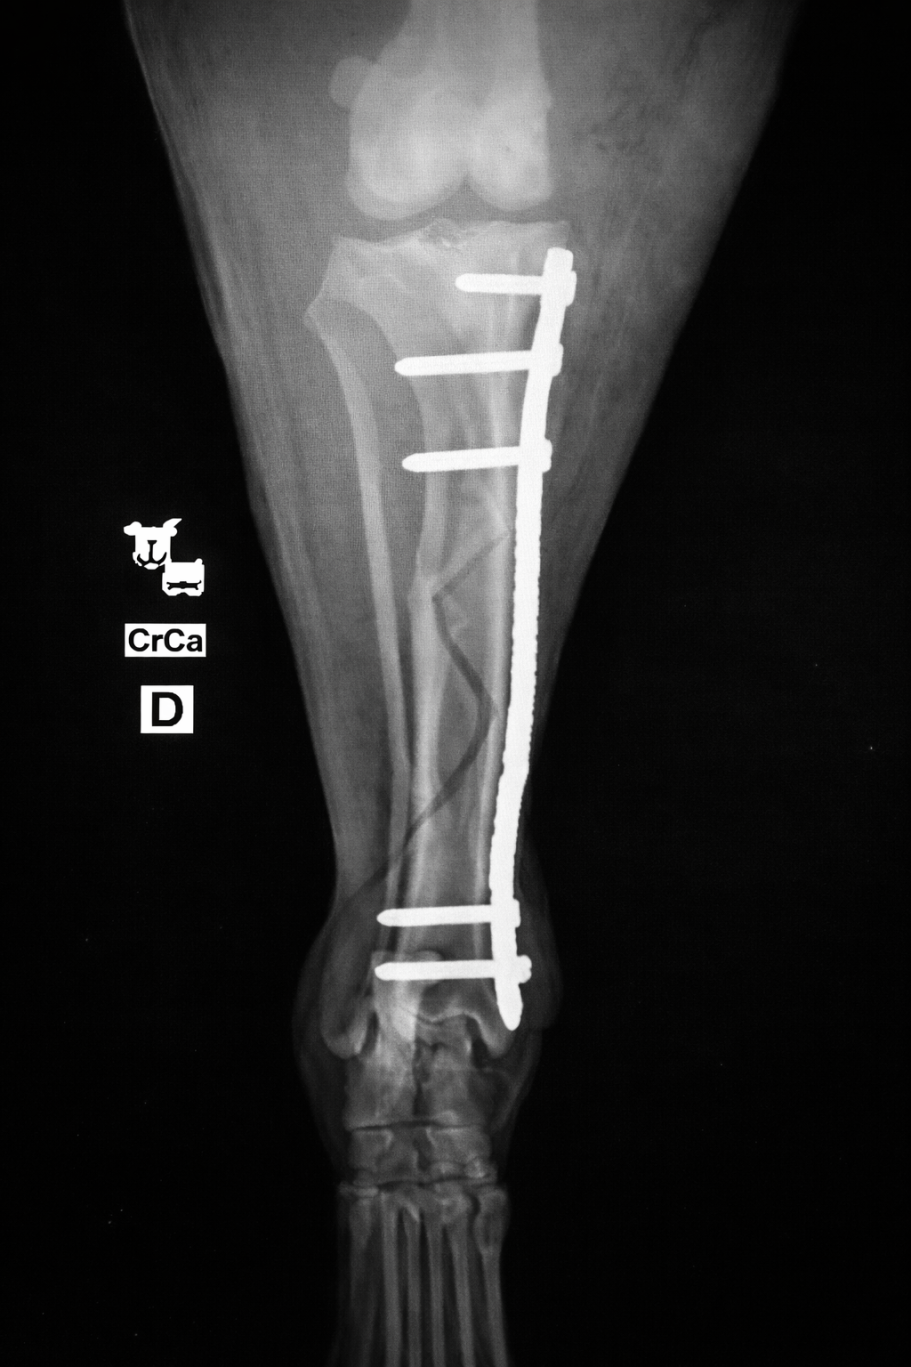

Frakturversorgung (Knochenbrüche)

Behandlung von Frakturen bei Hunden und Katzen mittels moderner Verfahren.

Ziel ist eine stabile Fixation, eine schnelle Heilung und die möglichst frühzeitige Wiederherstellung der Belastbarkeit.

Frakturversorgung mit Arthrex Implantate

Für die Behandlung von Knochenbrüchen verwenden wir moderne Implantate von höchster Qualität. Sie bieten eine sehr gute Stabilität und unterstützen eine sichere Heilung. Je nach Art der Fraktur kommen Implantate aus Titan oder hochwertigem chirurgischem Edelstahl zum Einsatz. Die Implantate sind in passenden Größen verfügbar und genau auf den Knochen und die Anatomie Ihres Tieres abgestimmt.